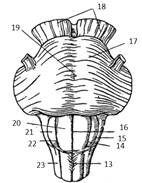

Сердце. Топография, внешнее строение

Различают три поверхности сердца:

грудино-реберную, диафрагмальную, легочную, а также правый край сердца.

Грудино-реберная поверхность выпуклая, касается грудной стенки только областью

верхушки. Диафрагмальная поверхность целиком прилегает к диафрагме, эта

поверхность сердца уплощена. Легочная поверхность, соответствующая сердечному

вдавлению левого легкого, выпуклая. Правый край входит в состав стенки правого

желудочка. На поверхности сердца находятся передняя и задняя межжелудочковые

борозды, охватывающие сердце спереди и сзади, и поперечная венечная борозда,

расположенная кольцеобразно.

В грудной полости сердце занимает косое

положение и обращено широкой частью – основанием кверху, назад и вправо, а

узкой – верхушкой вперед, вниз и влево, на две трети оно располагается в левой

половине грудной полости.

Строение сердца. Общие сведения

Сердце (cor) у человека четырехкамерное. В

сердце расположены продольные перегородки (межпредсердная -4 и межжелудочковая

– 14), которые делят орган на две изолированные половины – правое и левое

сердце, поперечная перегородка делит каждую из этих половин на верхнюю камеру –

предсердие и нижнюю – желудочек сердца.

Строение правого предсердия и желудочка

Правая половина сердца содержит венозную кровь и

состоит из правого предсердия (atrium dexstrum) и правого желудочка

(ventriculus dexter). Правое предсердие имеет форму куба, располагается в

основании сердца справа и позади аорты и легочного ствола. От левого предсердия

отделяется межпредсердной перегородкой (16), на которой находится овальная ямка

(15), которая является остатком овального отверстия через которое сообщаются

между собой предсердия во внутриутробном развитии. В правое предсердие впадает

верхняя полая вена (1), нижняя полая вена (14) и венечный синус (13). Верхняя

часть правого предсердия образована правым ушком сердца (5). Правое предсердие

сообщается с правым желудочком при помощи предсердно-желудочкового отверстия.

Правый желудочек имеет форму треугольной

пирамиды, с верхушкой обращенной вниз и располагается справа и спереди от

левого желудочка. От левого желудочка отделяется при помощи межжелудочковой

перегородки. Вверху в стенке желудочка есть два отверстия: сзади – правое

предсердно-желудочковое, а спереди – отверстие легочного ствола.

Предсердно-желудочковое отверстие закрывается при помощи трехстворчатого

клапана (8). Внутри правого желудочка находятся трабекулы и сосочковые мышцы,

от которых к створкам клапана идут сухожильные хорды. Из правого желудочка

начинается легочной ствол (6). Между правым желудочком и легочным стволом

находится полулунный клапан легочного ствола.

Строение левого предсердия и желудочка

Левая половина сердца содержит артериальную

кровь и состоит из левого предсердия (atrium sinistrum) и левого желудочка

(ventriculus sinister).

Левое предсердие имеет форму неправильного куба,

отграничено от правого межпредсердной перегородкой, имеет левое ушко (15). В

левое предсердие открываются 4 легочные вены, лишенные клапанов, они приносят

артериальную кровь от дёгких. С левым желудочком сообщается с помощью

предсердно-желудочкового отверстия, возле которого находятся гребенчатые мышцы.

Левый желудочек (16) конусовидный, его основание

обращено кверху. В переднем верхнем отделе желудочек сообщается с аортой. У

места выхода аорты из левого желудочка имеется клапан аорты, который состоит из

правой, левой и задней полулунных заслонок. В предсердно-желудочковом отверстии

располагается двухстворчатый клапан (митральный – 7).

На внутренней поверхности левого желудочка

находятся мясистые трабекулы (10) и две сосочковые мышцы (9), от которых идут

сухожильные хорды (8), прикрепляющиеся к свободным краям створок митрального

клапана.

Толщина стенок левого предсердия около 2 мм, а

желудочка – до 15 мм. Верхушку сердца полностью выполняет левый желудочек.